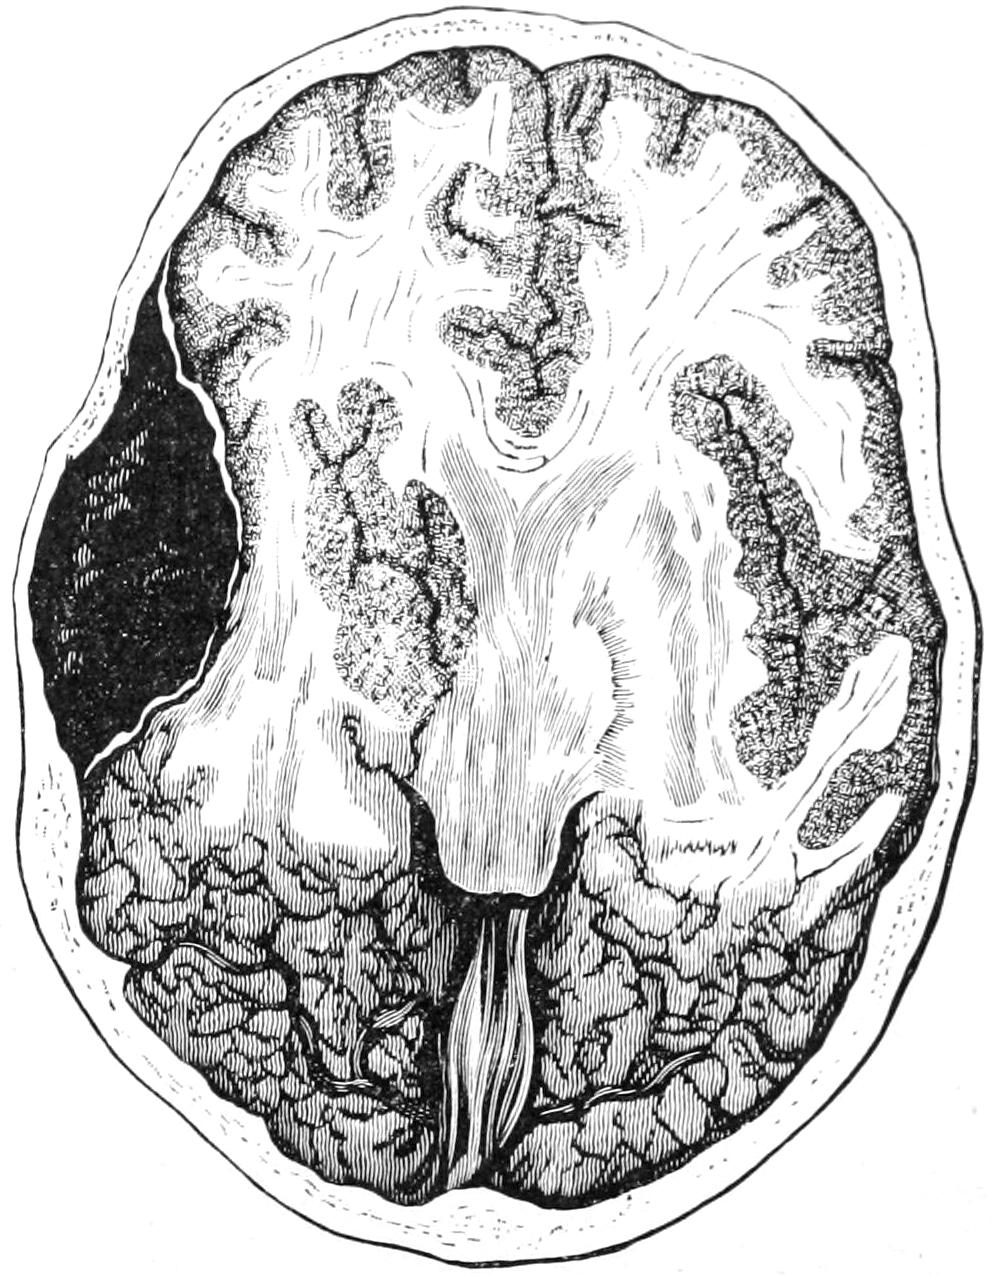

PLATE I

PLATE I.

BLOOD.

(Ehrlich triple stain.)

(Prepared by Dr. I. P. Lyon.)

Fig. I. TYPES OF LEUCOCYTES.

a. Polymorphonuclear Neutrophile. b. Polymorphonuclear Eosinophile. c. Myelocyte (Neutrophilic). d. Eosinophilic Myelocyte. e. Large Lymphocyte (large Mononuclear). f. Small Lymphocyte (small Mononuclear).

Fig. II. NORMAL BLOOD.

Field contains one neutrophile. Reds are normal.

Fig. III. ANÆMIA, POST-OPERATIVE (secondary).

The reds are fewer than normal, and are deficient in hæmoglobin and somewhat irregular in form. One normoblast is seen in the field, and two neutrophiles and one small lymphocyte, showing a marked post-hæmorrhagic anæmia, with leucocytosis.

Fig. IV. LEUCOCYTOSIS, INFLAMMATORY.

The reds are normal. A marked leucocytosis is shown, with five neutrophiles and one small lymphocyte. This illustration may also serve the purpose of showing the leucocytosis of malignant tumor.

Fig. V. TRICHINOSIS.

A marked leucocytosis is shown, consisting of an eosinophilia.

Fig. VI. LYMPHATIC LEUKÆMIA.

Slight anæmia. A large relative and absolute increase of the lymphocytes (chiefly the small lymphocytes) is shown.

Fig. VII. SPLENO-MYELOGENOUS LEUKÆMIA.

The reds show a secondary anæmia. Two normoblasts are shown. The leucocytosis is massive. Twenty leucocytes are shown, consisting of nine neutrophiles, seven myelocytes, two small lymphocytes, one eosinophile (polymorphonuclear) and one eosinophilic myelocyte. Note the polymorphous condition of the leucocytes, i. e., their variations from the typical in size and form.

Fig. VIII. VARIETIES OF RED CORPUSCLES.

a. Normal Red Corpuscle (normocyte). b, c. Anæmic Red Corpuscles. d-g. Poikilocytes. h. Microcyte. i. Megalocyte. j-n. Nucleated Red Corpuscles. j, k. Normoblasts. l. Microblast. m, n. Megaloblasts.

The value of a careful blood examination is well illustrated by Plate I, prepared by Dr. Irving P. Lyon, in which are displayed the alterations of greatest interest to the surgeon.